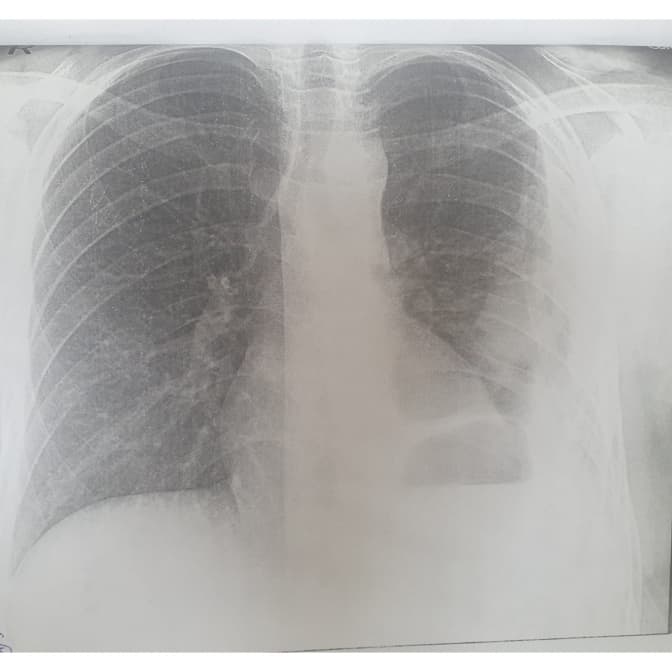

Львівські медики діагностували у Михайлика з Хмельниччини нагноєну кісту лівої легені великих розмірів із зміщенням середостіння вправо. Із такою вродженою вадою хлопчик прожив 10 років, не знаючи про це. Зі слів мами хлопчика, за життя дитині жодного разу не робили рентген, тому не могли знати про таку ваду.

Діагноз її вразив – те, що можна було діагностувати одразу після народження сина, виявили через 10 років. А за словами лікаря-хірурга Олега Леніва, кіста була настільки великою, що займала всю ліву половину грудної клітки. Із роками це спровокувало суттєве зміщення серця дитини в праву сторону.